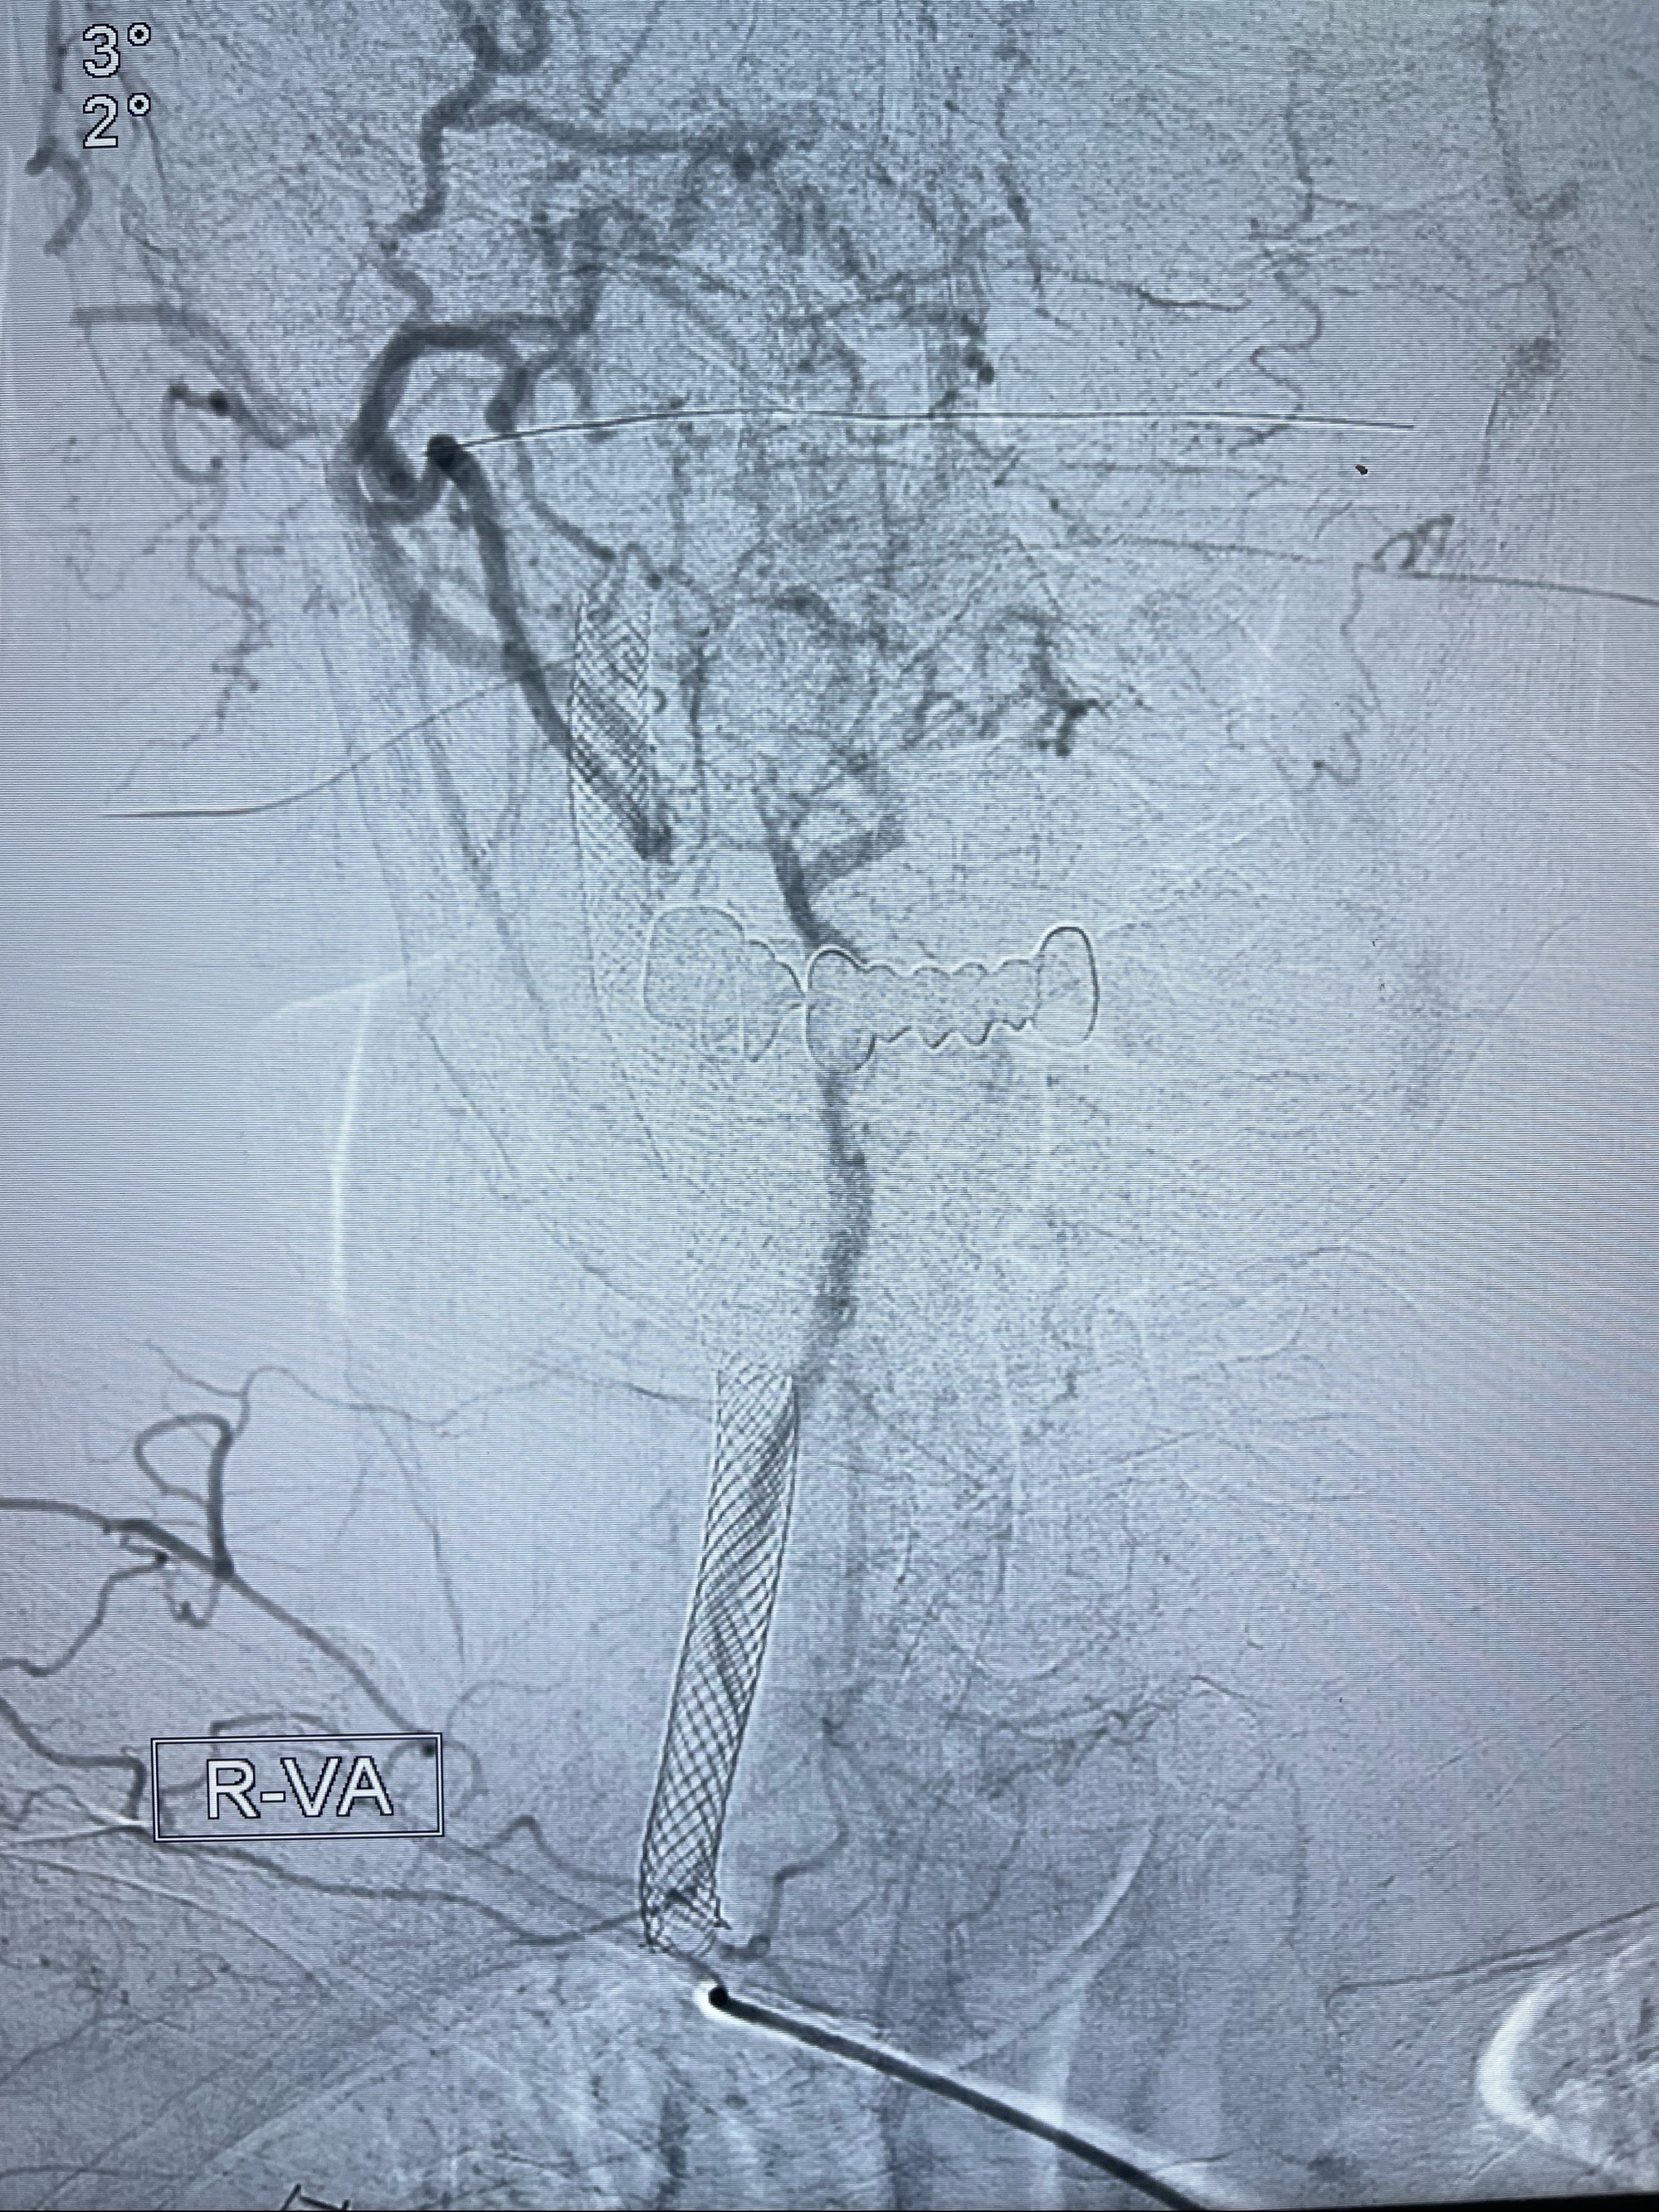

重新行“路径图”,支架导管在微导丝引导下超选择性插入至右侧颈内动脉眼段,4.5-50mmLeo支架释放,远心端位于海绵窦段,近心端位于岩骨段狭窄段以近

即刻造影显示支架贴壁佳

路径图下,5.5-50mmLeo支架导管在微导丝引导下超选择性插入远段Leo支架内

两枚支架部分重叠

多次确认支架位置及打开贴壁情况

支架完全打开,近心端位于原颈动脉支架远心端内